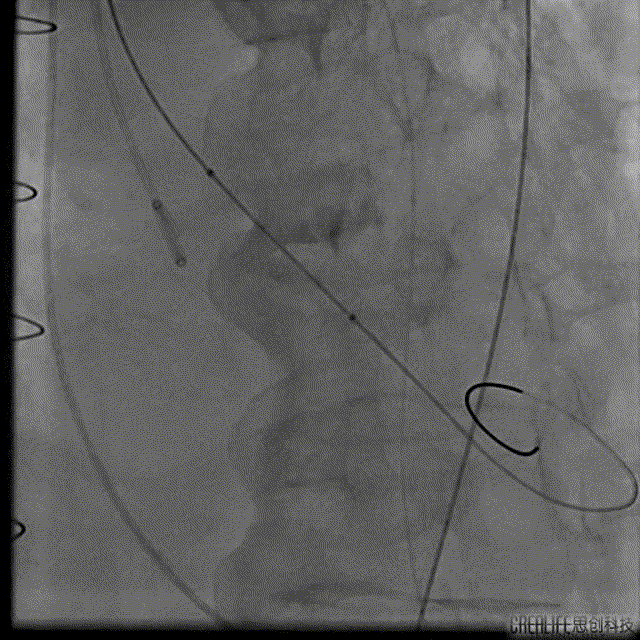

解剖上,这个患者虽然是右无融合的二叶瓣,但是右窦发育较小,形态上接近0型二叶瓣,瓣上钙化中,且集中在左窦,接近左右瓣叶联合部。瓣环及流出道平面较大,而瓣上结构较小,瓣叶联合部距离只有26,这种情况下只能考虑根据瓣上结构进行选择瓣膜。目标瓣膜为26号,为了避免破坏瓣上结构,我们选择26瓣膜的下限20号瓣膜进行与扩张。因为主动脉弓和升主动脉角度问题,没有选择plus。20球囊扩张可以看到左窦钙化很硬,右无联合可以推开,没有反流,故选择26号瓣膜,高位释放。释放后瓣膜下滑到标准位,有明显的腰,故用20球囊进行后扩展。最后造影虽然有中度瓣周漏,但是考虑患者狭窄解除,且升主动脉人工血管限制了瓣膜的流出端,未再行瓣中瓣。术中撤除ECMO,辅助循环约1小时。

手术过程: